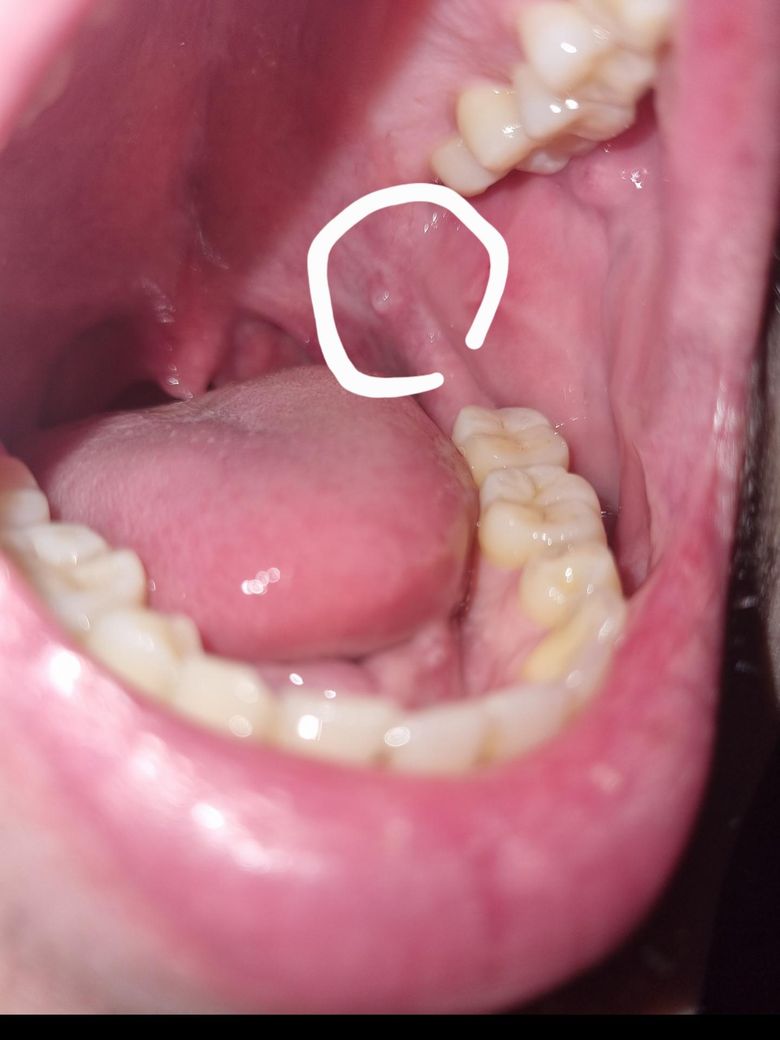

사진처럼 저렇게 혹같은게 생겼는데 저게 뭔가요?

혀로 닿으면 느낌이 이상하긴하네요 그냥 피곤해서 그런가보다 싶었는데 뭔가 찜찜해서 질문남겨봅니다...

단순 지방종일 가능성이 높아 보이나 정확한 판단을 위해서는 구강내과를 방문하여 검사를 한 번 받아보는 것이 좋습니다. 지금 상태에서 더 커지거나 혹시나 불편감 등이 갑자기 나타난다면 지체하지 마시고 바로 치과를 방문하는 것이 필요해보입니다. 모양이나 색으로 보았을 때 크게 문제가 있는 것으로 보이지는 않습니다.

사진 흐려 명확히 보이지는 않으나 소타액선 저류로 발생한 점액류로 추정됩니다. 해당부위 크기 작은 상태로 지켜보시다가 크기 변화 있을 시 구강악안면외과 등 내원하시는 것 권유드립니다.